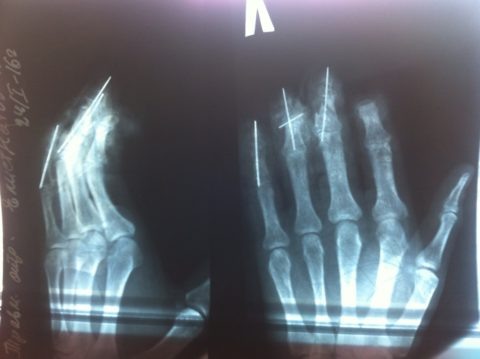

На снимке виден открытый краевой перелом среднего пальца на руке